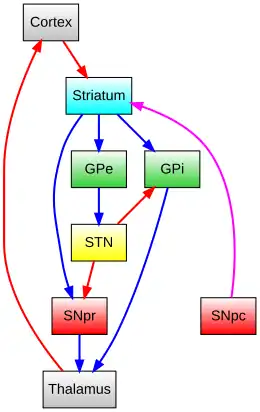

The nigrostriatal pathway influences movement through two pathways, the direct pathway of movement and the indirect pathway of movement.[29][30]

Direct pathway of movement

The direct pathway is involved in facilitation of wanted movements. The projections from dopamine D1 receptors containing medium spiny neurons in the caudate nucleus and putamen synapse onto tonically active GABAergic cells in the substantia nigra pars reticulata and the internal segment of the globus pallidus (GPi), which then project to the thalamus. Because the striatonigral / striatoentopeduncular and nigrothalamic pathways are inhibitory, activation of the direct pathway creates an overall net excitatory effect on the thalamus and on movement generated by the motor cortex.

Indirect pathway of movement

The indirect pathway is involved in suppressing unwanted movement. The projections from dopamine D2 receptors containing medium spiny neurons in the caudate nucleus and putamen synapse onto tonically active GABAergic cells in the external segment of the globus pallidus (GPe), which then projects to the substantia nigra pars reticulata via the excitatory subthalmic nucleus (STN). Because the striatopallidal and nigrothalamic pathways are inhibitory but the subthalamic to nigra pathway is excitatory, activation of the indirect pathway creates an overall net inhibitory effect on the thalamus and on movement by the motor cortex.